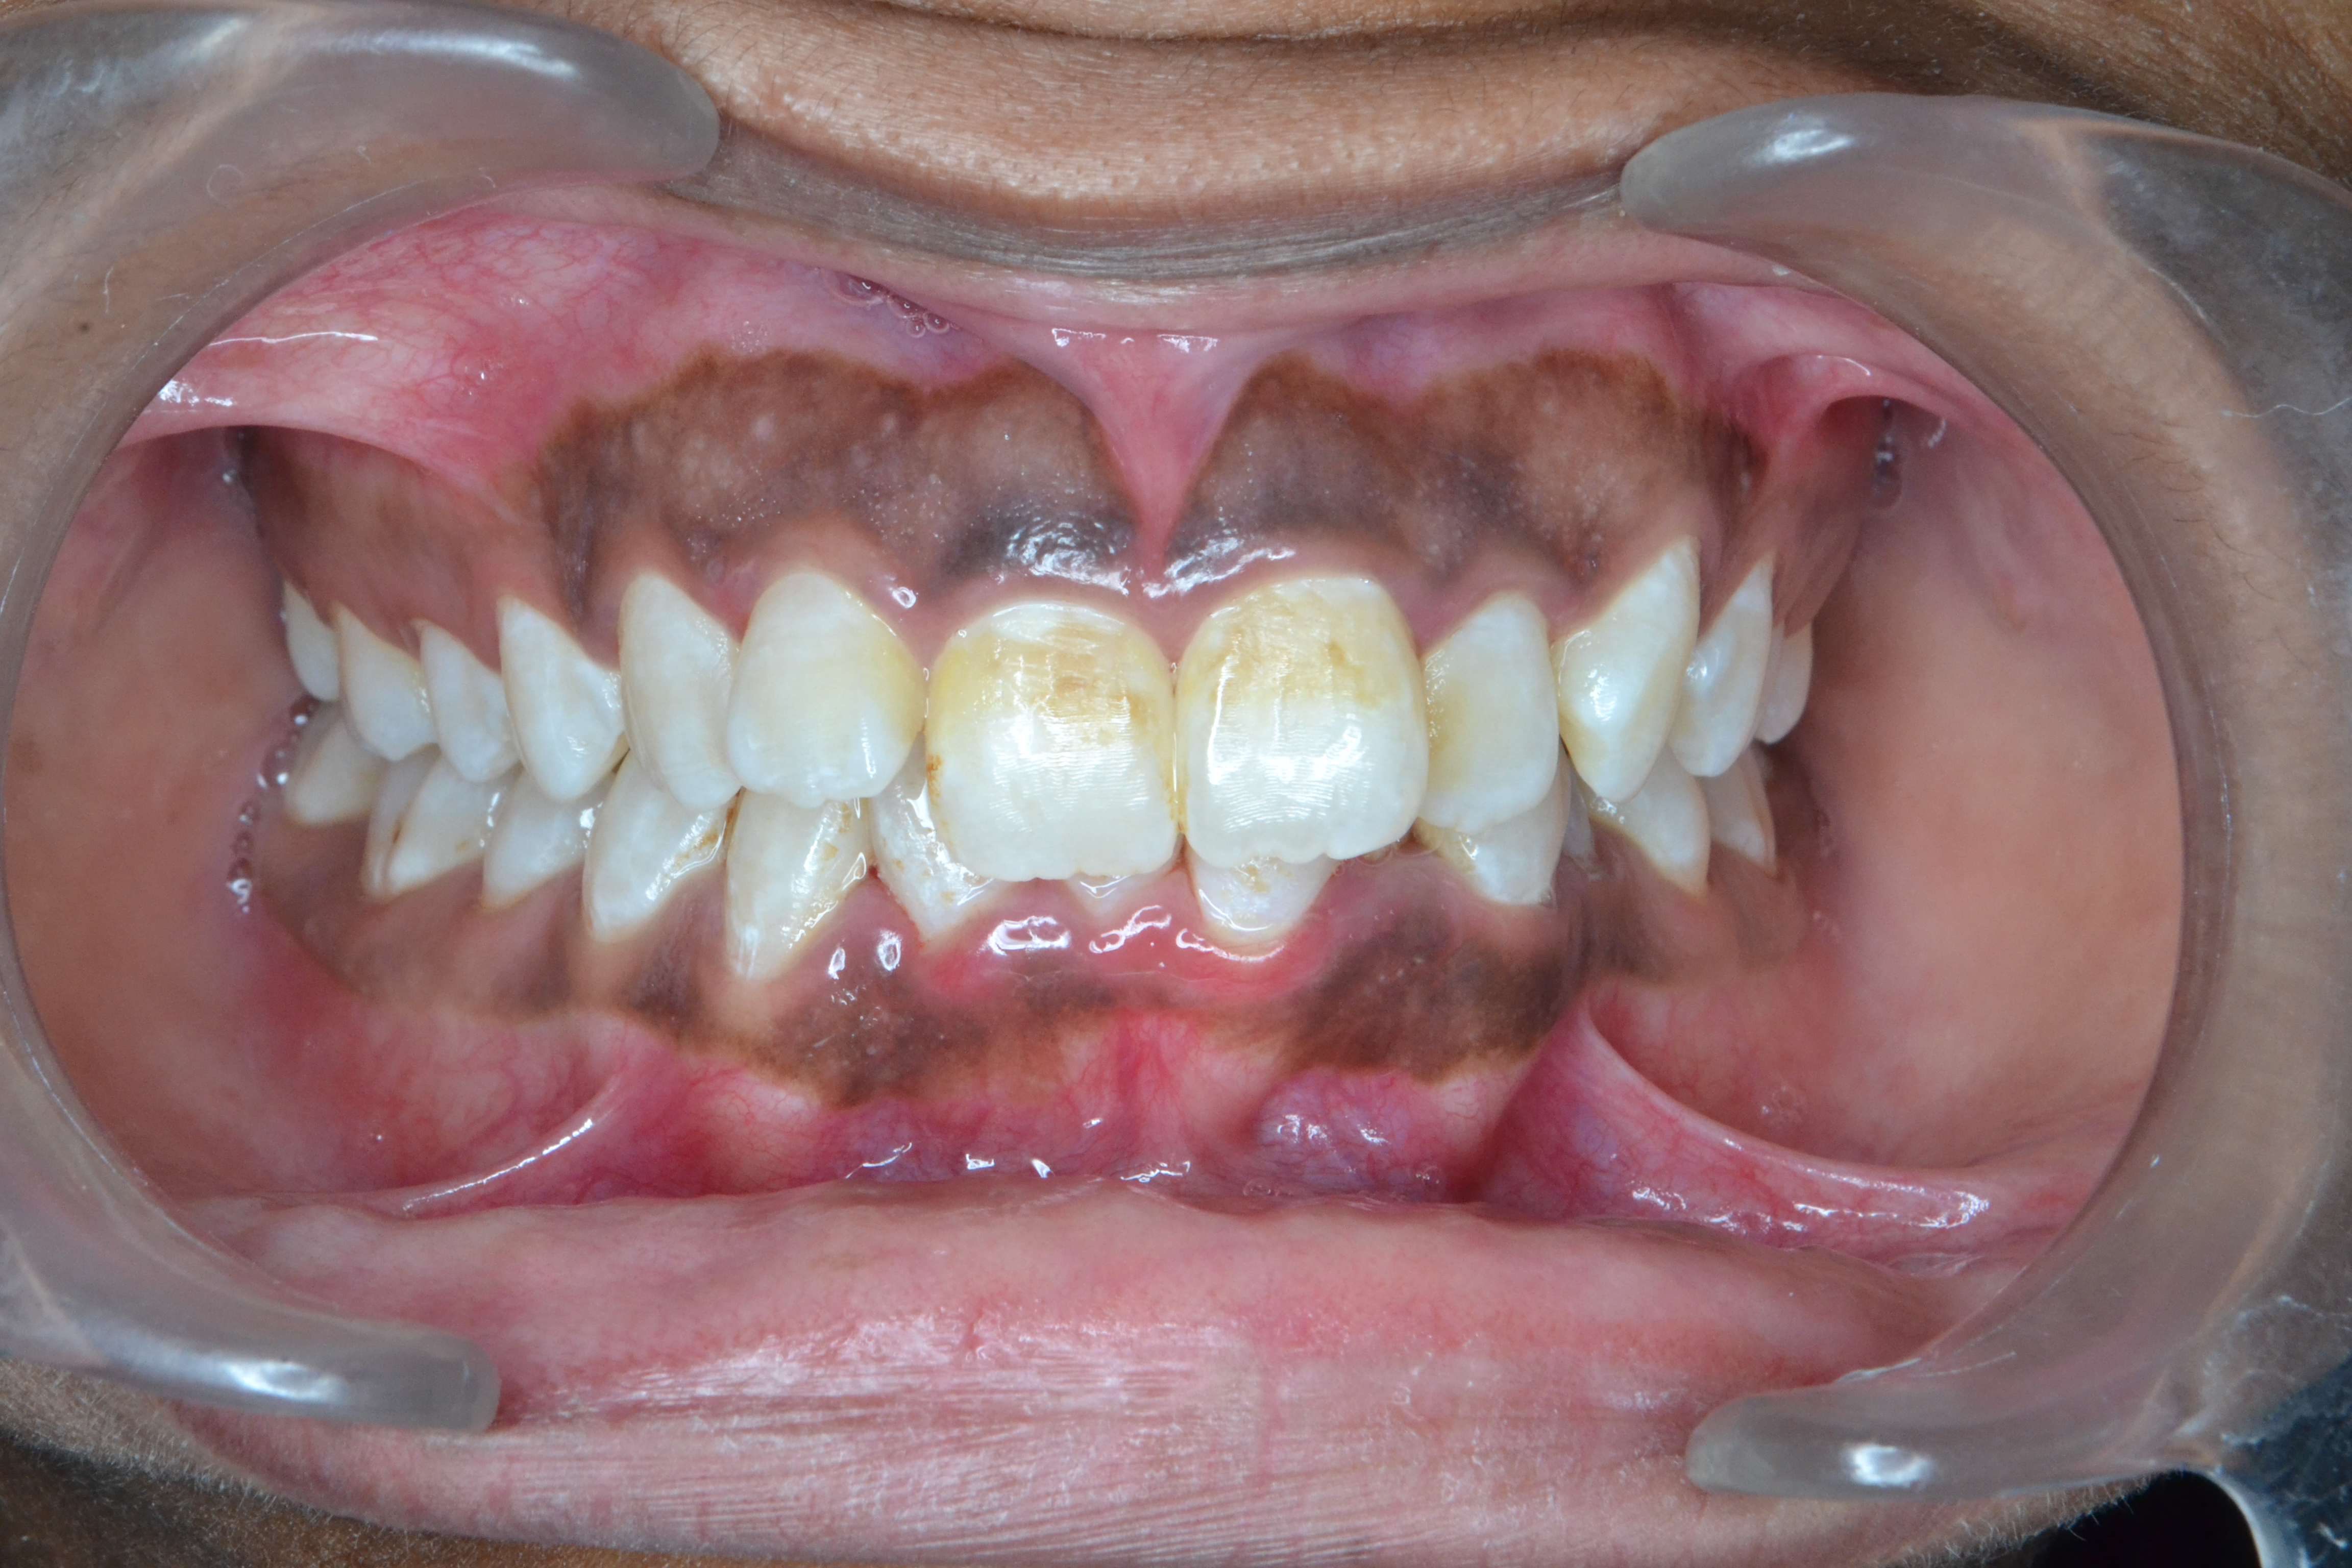

Sairam dental care located in Dharmapuri, with Leading Dentist In Oddapatti, is the Dental Hospital with exclusive root canal, Braces & Invisalign center. Led by renowned Drs Raghuraaman ( Periodontist) and Nivetha Raghuraaman ( Orthodontist) Sairam dental care offers gum treatment with expertise in laser, root canal treatment and digital smile correction with advanced technology aim to focus on aesthetics, comfort and precision. The clinic also specializes in Invisalign treatment, digital smile makeover, laser gum care, dental implants, root canal therapy, extractions and full-mouth rehabilitation blending compassionate care and clinical excellence.